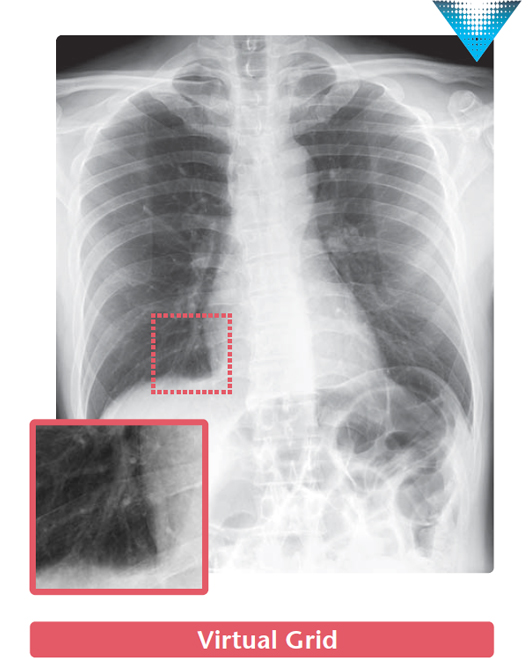

Image processing that remove the scatter X-rays from the digital radiography created without a physical grid.

Virtual Grid is an image processing software that corrects for the effects of scatter X-rays that otherwise reduce image contrast and clarity.

Without the need for physical grid, this software quickly predicts and then corrects for the effects of scatter X-rays, creating an improved image quality.

High quality images can be obtained under low dose conditions, thus reducing the amount of radiation does the patient receives*4.

- *4 In CD-RAD phantom evaluations performed by FUJIFILM, when compared with images acquired with an 8:1 grid, comparable non-grid images processed with Virtual Grid software yielded a 50% reduction in dose.

Virtual Grid allows setting of the grid ratio, number of grid lines and interspace material, and examinations using the appropriate grid conditions.

Just as for a physical grid, different Virtual Grid settings can be used, best suited for the different regions and exposure conditions.

Of course, as it is a virtually created grid, the grid type can be changed after an exposure